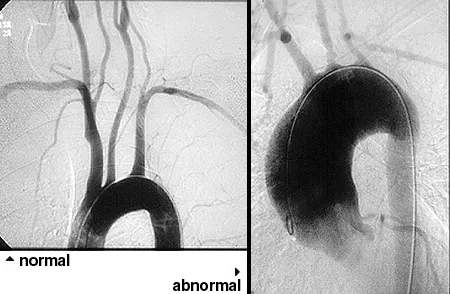

- Imaging: CT or MR Angiography (CTA/MRA) is the gold standard to visualize vessel wall thickening and stenosis.

| Imaging | Ultrasound: "Halo sign" (edema) | MRA/CTA: Aortic/branch stenosis, wall thickening |

⭐ Visual confirmation is key: A positive "halo sign" on temporal artery ultrasound is highly specific for GCA, while angiography revealing stenosis or aneurysms of the aorta and its main branches is the cornerstone of Takayasu diagnosis.